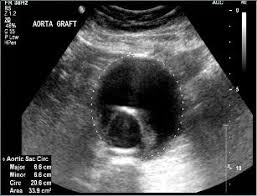

Examination of the arteries and/or veins within the abdomen, most commonly to assess for the presence of an abdominal aortic aneurysm (AAA) but may also be used to assess the abdominal branches of the aorta for abnormalities. Fasting may be required for assessment of the abdominal vessels.

In the case of a AAA the most common type of repair carried out is an endovascular repair using a graft that is inserted within the vessel to seal off the area of abnormal dilatation. Regular follow-up scans of the graft can be carried out to ensure continued patency and that there are no leaks around the synthetic graft.